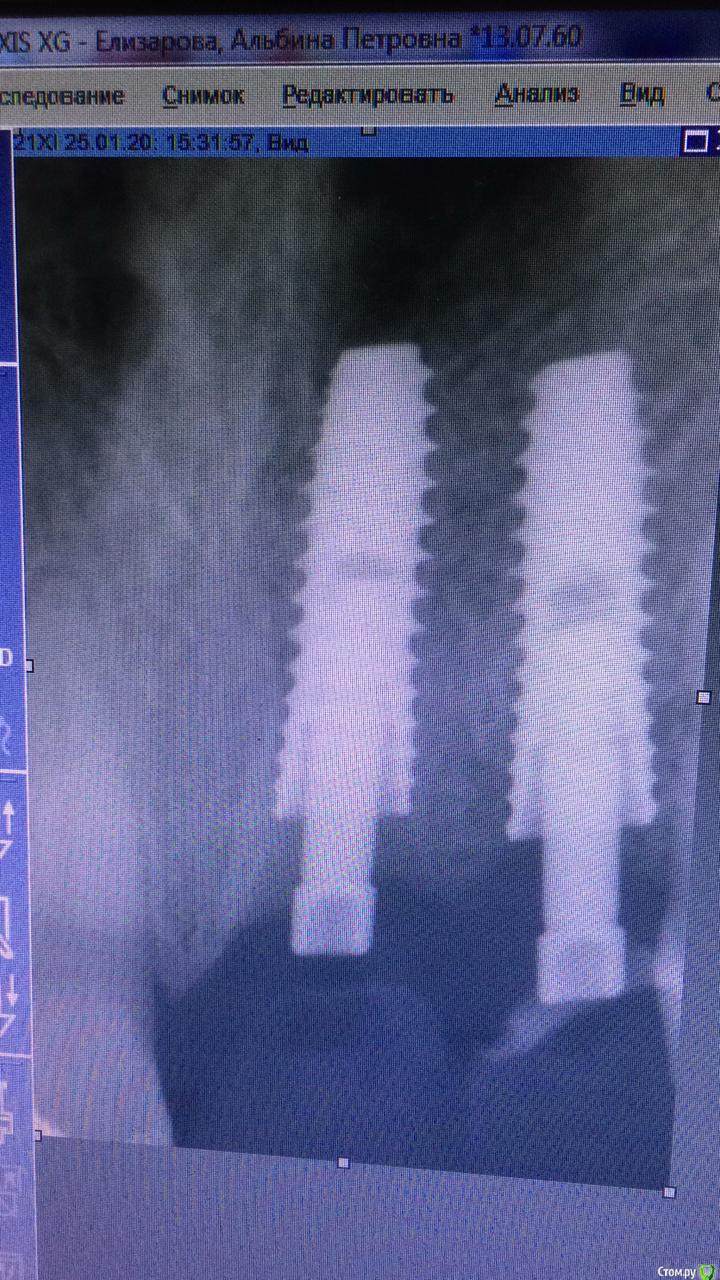

жулля Опубликовано 4 февраля, 2020 Поделиться Опубликовано 4 февраля, 2020 Добрый вечер! 23.11.19г. мне сделали одномоментную имплантацию двух передних зубов системой Имплантиум. и все 2 месяца у меня ощущения дискомфорта , то легкой боли при нажатии на десну, постоянно какие то ощущения. Я чувствую это место. ВРач говорит, что все хорошо. Очень переживаю за приживаемость, так почти везде пишут, что ничего не должно болеть. Языком надавливать сзади тоже чувствительность есть. Что посоветуете? Ссылка на комментарий

Irouil Опубликовано 4 февраля, 2020 Поделиться Опубликовано 4 февраля, 2020 Судя по всему, одна коронка недоприкручена, это может приводить к ее микроподвижности, попаданию пищи под десну. Ничего криминального, но, учитывая тот факт, что коронки связаны, я бы попробовал снять их и после проверки прикрутить заново. Но ситуация пограничная, сейчас период самый ненадёжный для механического воздействия на имплантаты, поэтому если в полости рта при осмотре доктор не видит повода для беспокойства, то, возможно, более рационально подождать ещё месяц-полтора, а пока в Вашу задачу будет входить идеальная гигиена вокруг имплантата с ежедневным использованием ирригатора Ссылка на комментарий

red_butler Опубликовано 5 февраля, 2020 Поделиться Опубликовано 5 февраля, 2020 + 1 открутить коронки, судя по снимкам формирователь десны упирался в край лунки, возможно и коронка/ки упираются, и лучше абатменты заменить на пластиковые. По Кт посмотрим взаимоотношение импланта и дна носа Ссылка на комментарий

red_butler Опубликовано 5 февраля, 2020 Поделиться Опубликовано 5 февраля, 2020 У меня не было формирователя десны. Было удаление, установка импланта и сразу коронокНа одном из снимков имплантаты с Формирователями Ссылка на комментарий

жулля Опубликовано 5 февраля, 2020 Автор Поделиться Опубликовано 5 февраля, 2020 На одном из снимков имплантаты с Формирователямиможет быть это самый первый снимок, ортопед опаздывал) Ссылка на комментарий